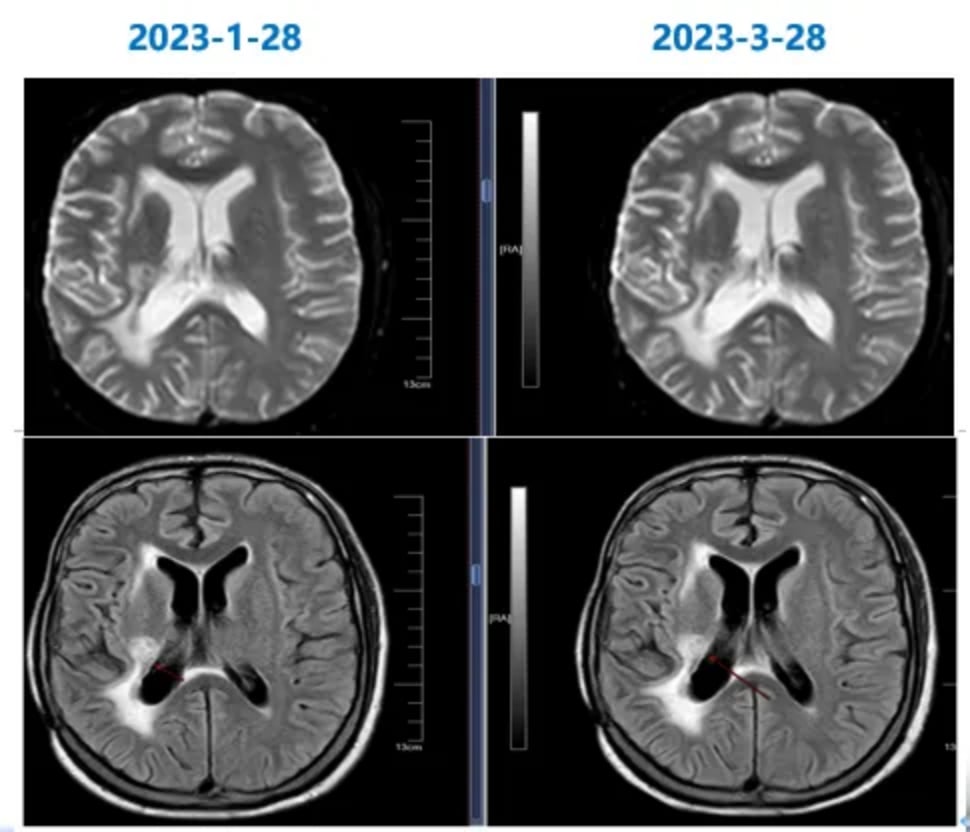

患者为一名49岁男性,因间断性头痛、恶心呕吐入院。颅脑MRI检查提示右侧颞叶存在占位性病变。

图1 初诊时颅脑MRI图像

2020年12月,患者接受了脑病损切除术。术后病理结果明确诊断为:右侧颞叶星形胶质细胞瘤,WHO IV级。基因检测结果显示,存在TERT突变、EGFR扩增,且MGMT启动子呈甲基化阳性。这些分子特征共同指向了预后不良的可能。